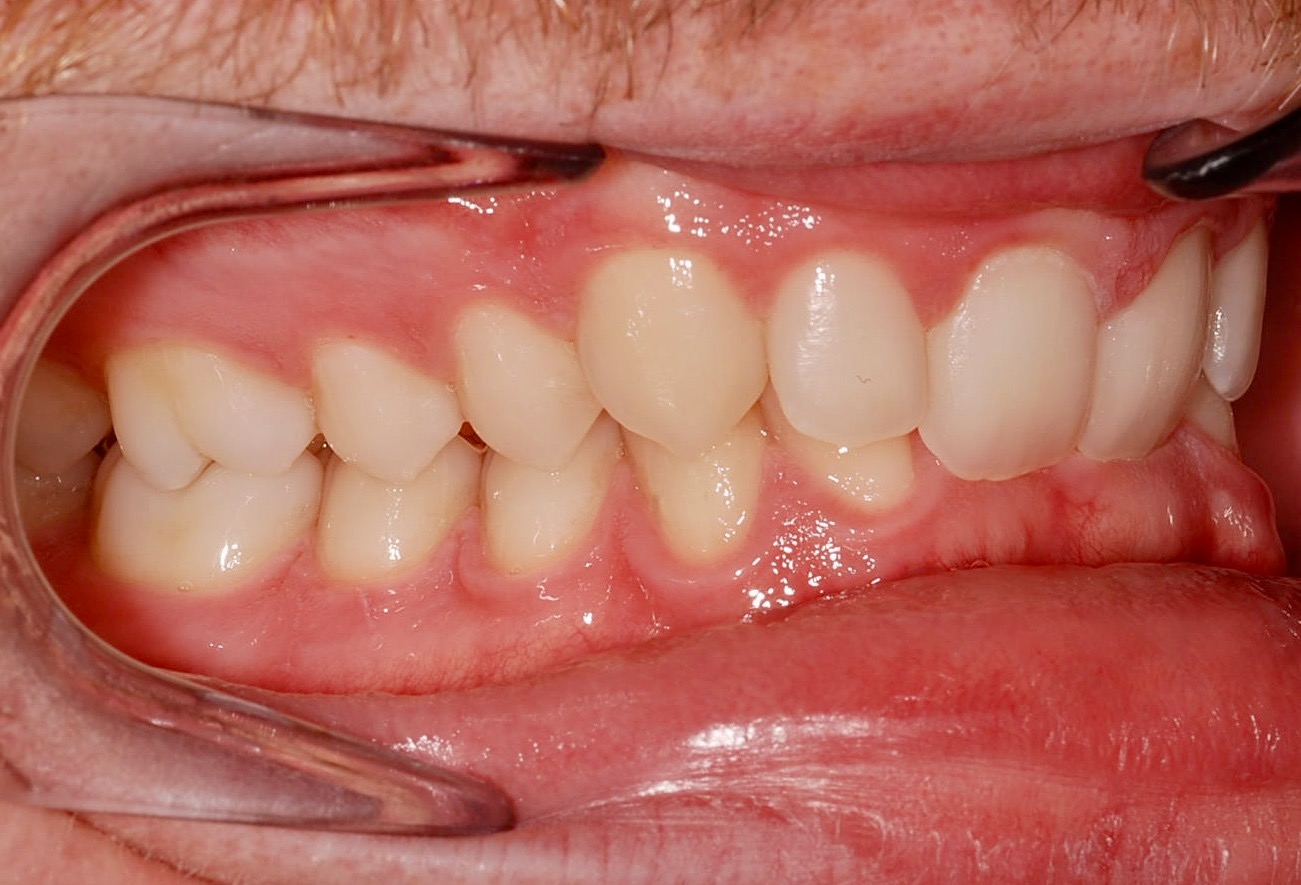

Class II subdivision malocclusions can be difficult to treat because of their asymmetric occlusal relationships. An accurate diagnosis, etiologically based when possible, is essential to perform a correct and efficient orthodontic treatment.

The aim of this article is to illustrate a case report treated with customized lingual brackets in association with a simple vestibular device.